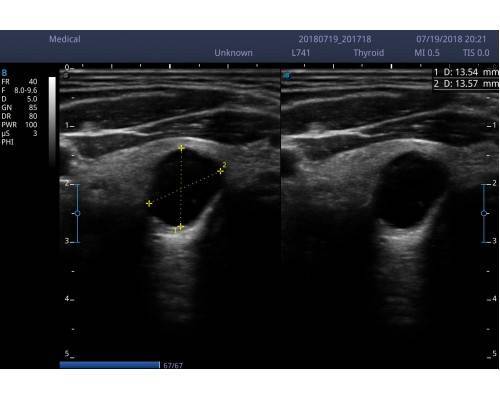

και μοντέρνας εμφάνισης του. Εξυπηρετεί τις ανάγκες όλων σχεδόν των ειδικοτήτων

Προηγμένες τεχνολογίες όπως m-scan,compound, THI,auto trace, auto IMT

(αυτόματος εντοπισμός πάχυνσης ενδοθηλίου καρωτίδας) με ενσωματωμένη μπαταρία.

• Εικόνα 2 διαστάσεων 2D (B mode),2B(δίπλες εικόνες), 4B(τετραπλές εικόνες), M mode, PW (pulse wave Doppler,CFM (color),PDI(power)DirPDI (κατεύθυνση ροής )CW .

L741 (VASCULAR-SMALL PARTS-MSK) 4.0-16.0 MHZ 46mm